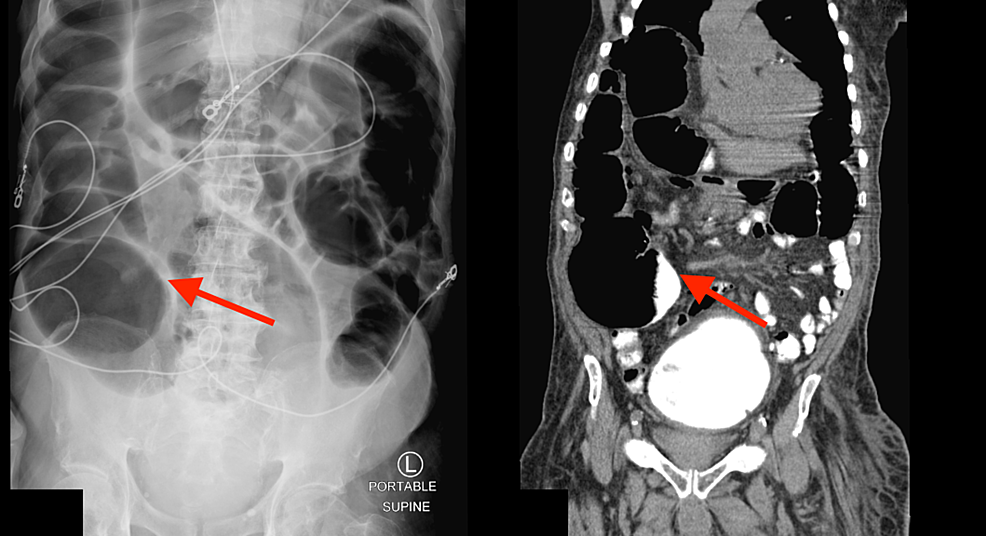

Endoscopic Decompression For Acute Colonic Pseudo-Obstruction . acute colonic distension is a medical emergency with high morbidity. On completion of this article, the reader should be able to review diagnostic testing confirming diagnosis of acute. this experience demonstrates that colonoscopic decompression with decompression tube placement is safe. patients that fail medical therapy may benefit from colonoscopic decompression or surgical decompression. efficacy, safety, and outcome of endoscopic decompression was assessed.

On completion of this article, the reader should be able to review diagnostic testing confirming diagnosis of acute. acute colonic distension is a medical emergency with high morbidity. this experience demonstrates that colonoscopic decompression with decompression tube placement is safe. patients that fail medical therapy may benefit from colonoscopic decompression or surgical decompression. efficacy, safety, and outcome of endoscopic decompression was assessed.